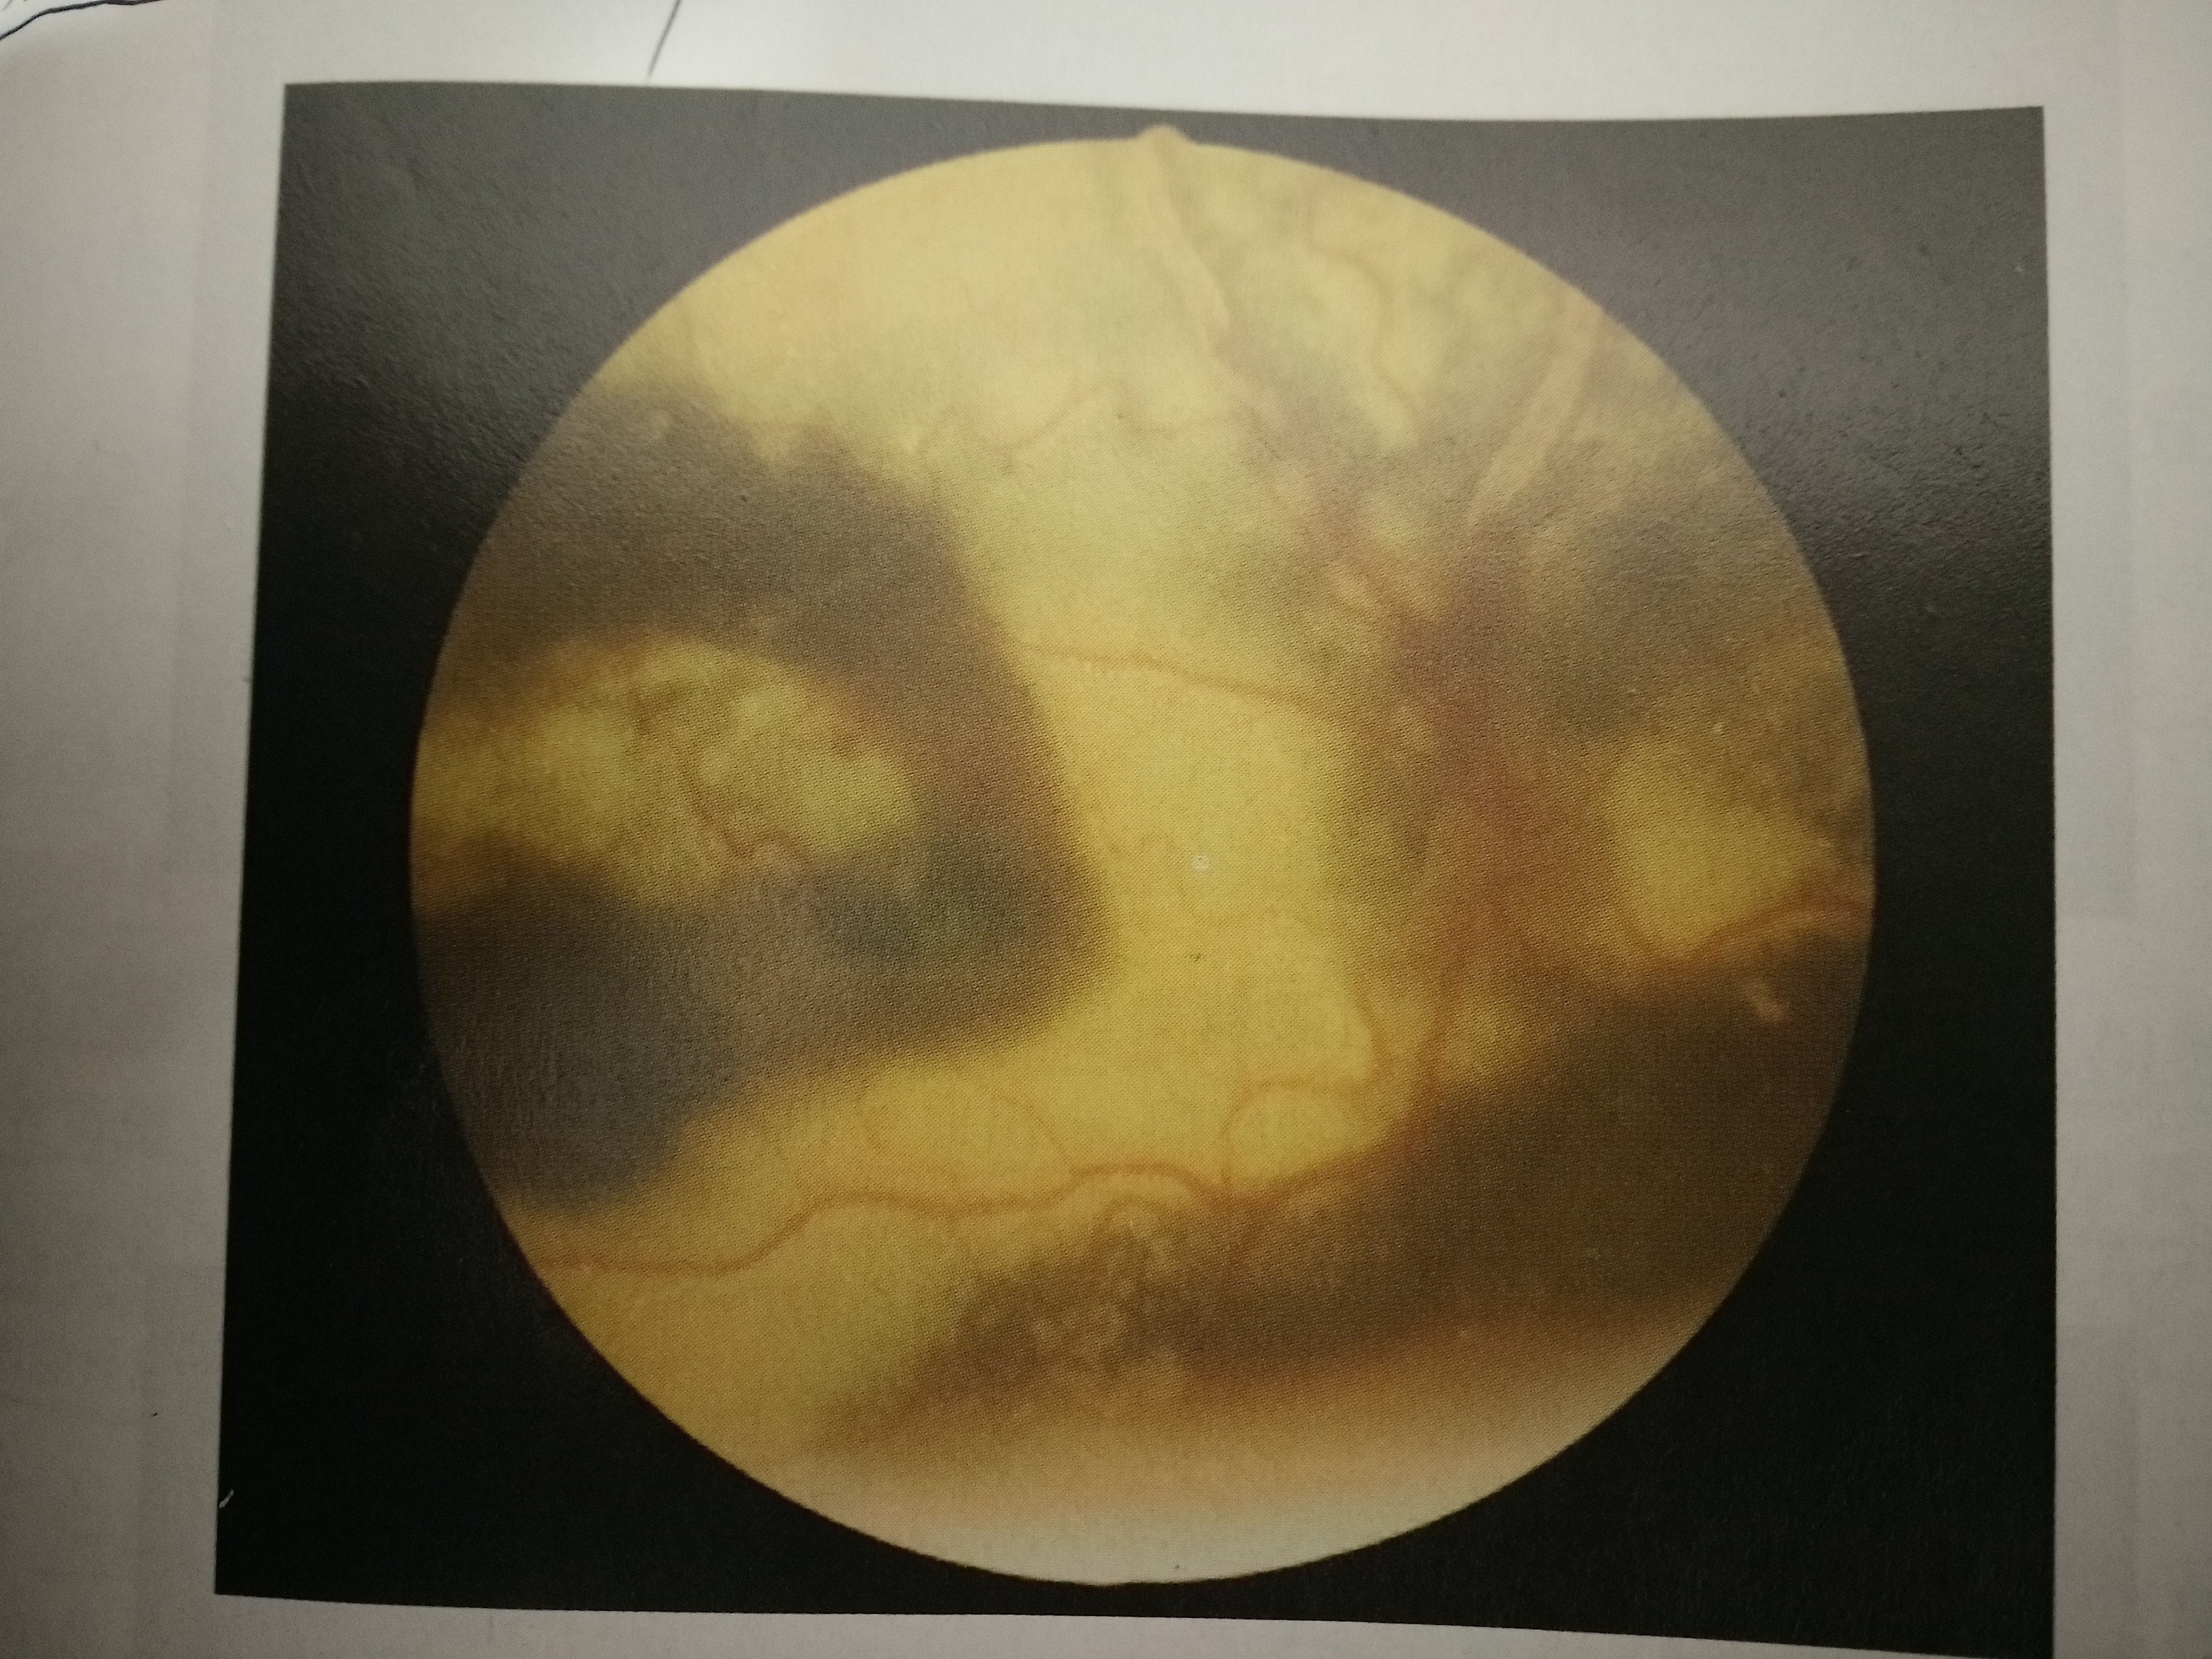

外层渗出性视网膜病变(coats病)

疾病科普|外层渗出性视网膜病变